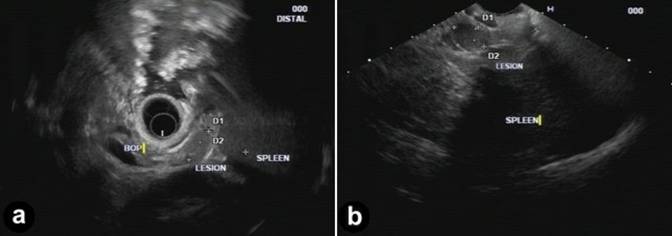

A 33-year-old lady presented with a three month history of dyspepsia. During evaluation, a 1.5 cm, homogenous, sharply defined lesion in the tail of the pancreas was seen on computed tomography (CT) scan of the abdomen and later confirmed by magnetic resonance imaging (MRI). The initial (pre-EUS) read on the CT and MRI suggested an enhancing intrapancreatic lesion concerning for a neuroendocrine tumor. Continued investigations included a negative Octreotide scan for pancreatic tumor localization. After being referred to our institution, review of radiological images suggested intrapancreatic accessory spleen since the signal intensity of the lesion was similar to the spleen on pre- and post-contrast CT and MRI sequences (Figure 1). Endosonography revealed a 1.5 cm, oval shaped, well-defined, homogeneous, hypoechoic lesion with similar echogenicity of the spleen (Figure 2). The pancreatic body and duct appeared normal. Two passes were made using a 22-guage needle for fine needle aspiration (FNA). The FNA showed normal pancreatic acinar tissue adjoining splenic pulp (Figure 3a) displaying extramedullary hematopoiesis (Figure 3b) and prominent vascularity (Figure 3c). Immunostaining with CD8 highlighted the sinus endothelial cells (Figure 3d) confirming diagnosis of intra-pancreatic accessory spleen.

Figure 2. a. Radial endosonography demonstrates a 1.5 cm, oval shaped, homogeneous, hypoechoic lesion with sharp, well defined borders in the tail of the pancreas and has similar echogenicity of the spleen. b. Linear endosonography confirms the same 1.5 cm hypoechoic lesion for fine needle aspiration. |